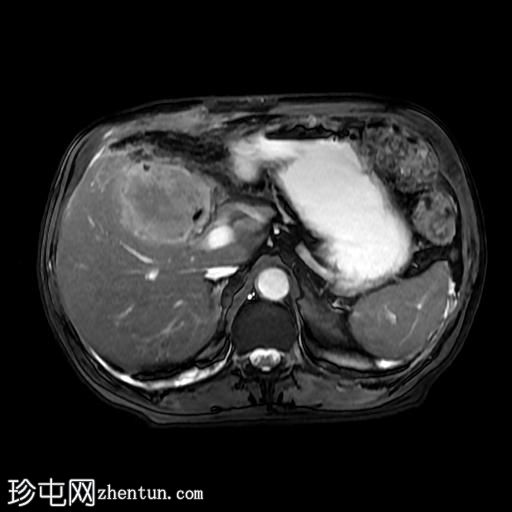

MRI

轴位T2加权像

胆囊切除术后,可见肝总管局部断裂,尤其是在胆囊管开口上方。该断裂伴有胆囊切除部位形成较大的血肿或胆汁瘤。

胆管损伤可能发生在手术过程中,导致胆汁渗漏到周围组织,从而形成血肿或胆汁瘤。这可能出现明显的临床症状,并可能需要进一步干预,具体取决于病情的严重程度和患者的临床表现。